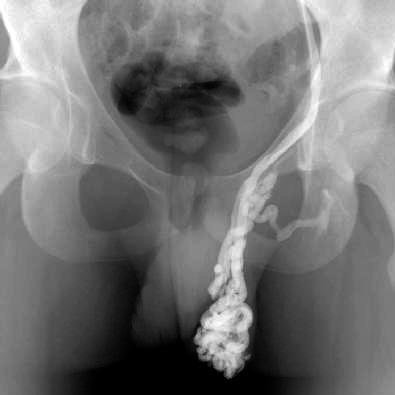

Varicocele

Varicocele¿Qué es el varicocele?

Consiste en la presencia de dilataciones varicosas (varices) en las venas que drenan la sangre de los testículos.

Hay varias aunque algunas han caído en desuso. La más frecuentemente utilizada es la ecografía-doppler.